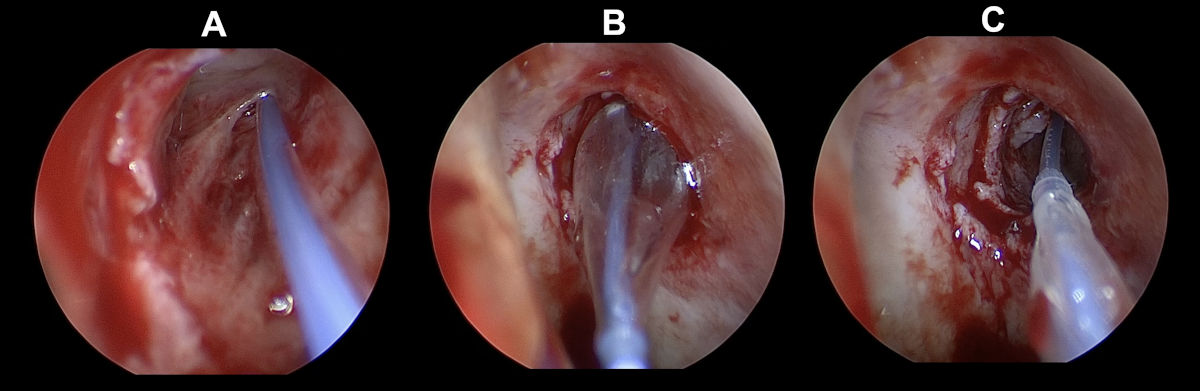

A 4 mm coronary balloon catheter (Boston Scientific, USA) was used to conduct a balloon dacryoplasty on the patient's left side (Fig. 10). An incision was made in the scar tissue developed after the previous DCR surgery (Fig. 11). The balloon catheter was introduced into the nasal cavity through the lacrimal canaliculus, lacrimal sac and the incised scar tissue. The catheter was inflated to 8 atm for 90 seconds, then it was deflated and removed (Fig. 12-13). After debriding the neo-ostium's periphery scar tissues, Mitomycin-C was applied. A significant internal common opening was visible in the immediate postoperative period. The ostium was big, anatomically correct, and functionally patent at the 3-month follow-up. At six months of follow-up, the patient was symptom-free and still receiving immunosuppressive treatment (Fig. 14-15).

Figure 13. Endoscopy view of the left nasal cavity: balloon dacryoplasty (A- guide wire being introduced, B - balloon catheter being inflated, C - balloon catheter being deflated; note enlarged ostium).